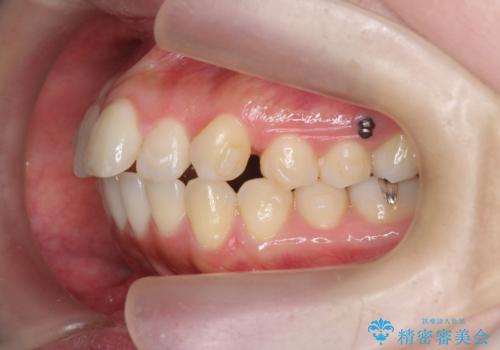

- 前歯の角度の改善を求めて矯正治療を希望し来院されました。

上下の歯は、上顎の歯が相対的に前に位置する咬合関係で押し出されるように前歯に角度がついている状態です。

咬合関係の改善、前歯の角度、がたつきを改善するため、マイクロインプラントを用いて上顎の奥歯を後方へ移動させていきます。